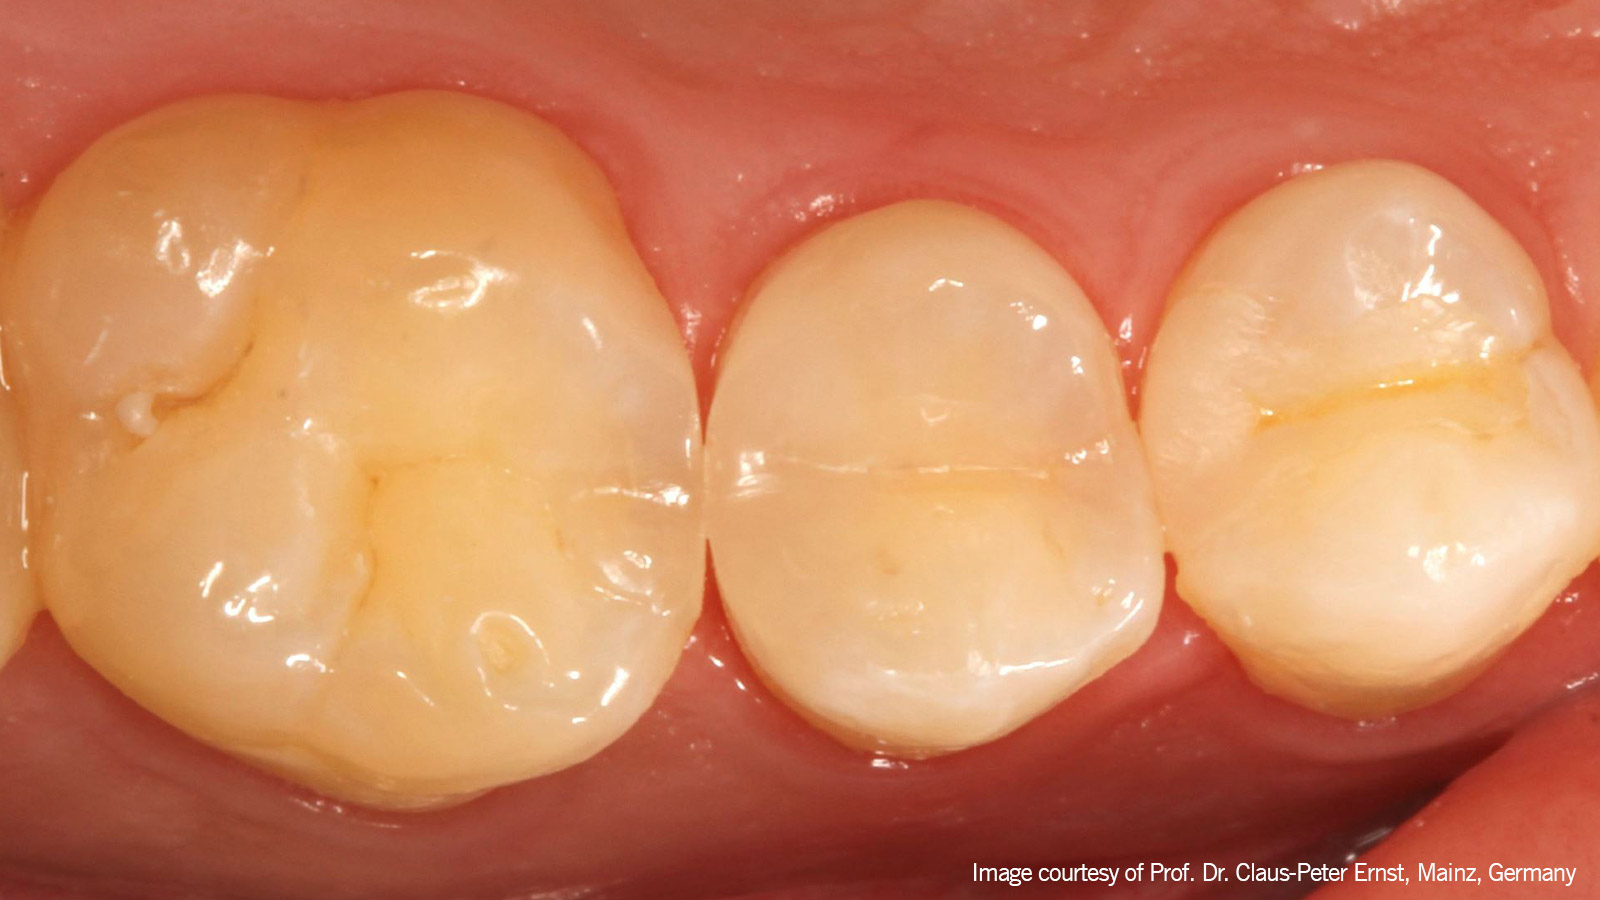

Polished

De afgewerkte en gepolijste nieuwe restauratie van element 15 bij een vervolgbezoek na 6 weken. Het ongemak is inmiddels al aanzienlijk verminderd.